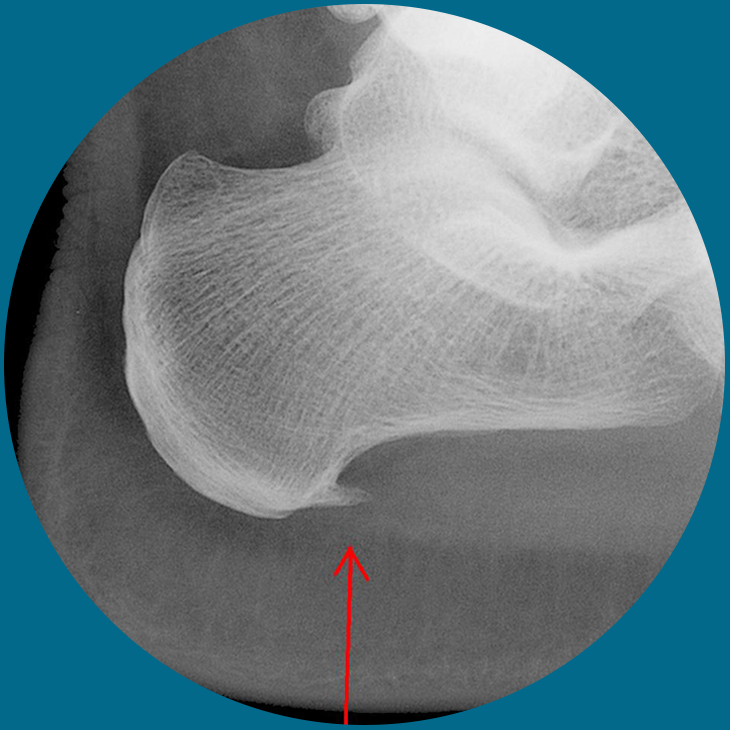

Heel Spurs

The heel bone is the largest bone in the foot and absorbs the most amount of shock and pressure. A heel spur develops as an abnormal growth of the heel bone. Calcium deposits form when the plantar fascia pulls away from the heel area, causing a bony protrusion, or heel spur to develop. The plantar fascia is a broad band of fibrous tissue located along the bottom surface of the foot that runs from the heel to the forefoot. Heel spurs can cause extreme pain in the rearfoot, especially while standing or walking.

Heel spurs develop as an abnormal growth in the heel bone due to calcium deposits that form when the plantar fascia pulls away from the heel. This stretching of the plantar fascia is usually the result of over-pronation, but people with unusually high arches can also develop heel spurs. Women have a significantly higher incidence of heel spurs due to the types of footwear often worn on a regular basis.

The heel bone is the largest bone in the foot and absorbs the most amount of shock and pressure. A heel spur develops as an abnormal growth of the heel bone. Calcium deposits form when the plantar fascia pulls away from the heel area, causing a bony protrusion, or heel spur to develop. The plantar fascia is a broad band of fibrous tissue located along the bottom surface of the foot that runs from the heel to the forefoot. Heel spurs can cause extreme pain in the rearfoot, especially while standing or walking.

Heel spurs develop as an abnormal growth in the heel bone due to calcium deposits that form when the plantar fascia pulls away from the heel. This stretching of the plantar fascia is usually the result of over-pronation, but people with unusually high arches can also develop heel spurs. Women have a significantly higher incidence of heel spurs due to the types of footwear often worn on a regular basis.